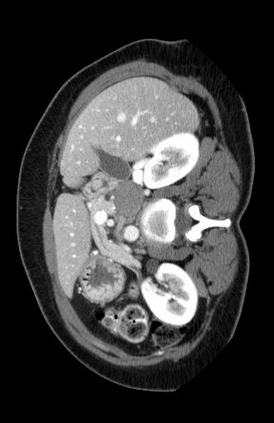

Vision foundation models like the Segment Anything Model (SAM), pretrained on large-scale natural image datasets, often struggle in medical image segmentation due to a lack of domain-specific adaptation. In clinical practice, fine-tuning such models efficiently for medical downstream tasks with minimal resource demands, while maintaining strong performance, is challenging. To address these issues, we propose BALR-SAM, a boundary-aware low-rank adaptation framework that enhances SAM for medical imaging. It combines three tailored components: (1) a Complementary Detail Enhancement Network (CDEN) using depthwise separable convolutions and multi-scale fusion to capture boundary-sensitive features essential for accurate segmentation; (2) low-rank adapters integrated into SAM's Vision Transformer blocks to optimize feature representation and attention for medical contexts, while simultaneously significantly reducing the parameter space; and (3) a low-rank tensor attention mechanism in the mask decoder, cutting memory usage by 75% and boosting inference speed. Experiments on standard medical segmentation datasets show that BALR-SAM, without requiring prompts, outperforms several state-of-the-art (SOTA) methods, including fully fine-tuned MedSAM, while updating just 1.8% (11.7M) of its parameters.